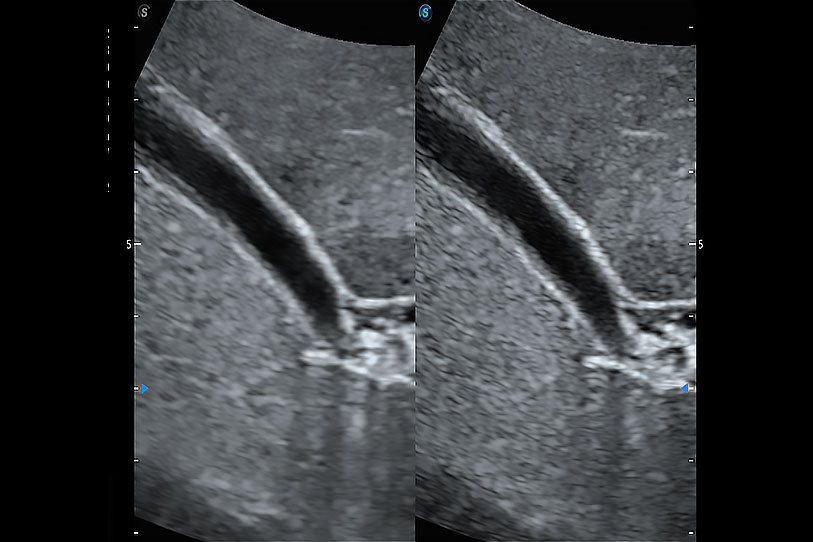

增強(qiáng)穿刺針在動物解剖結(jié)構(gòu)中的位置,提高穿刺介入的安全性和準(zhǔn)確性。

通過創(chuàng)新的 Matrix E自適應(yīng)濾波器和超長時間域算法,極大提升超低速微細(xì)血流的檢出能力,同時更精準(zhǔn)地濾除軟組織和噪聲信號,為獸用醫(yī)生提供以往無法通過常規(guī)血流獲得的疾病診斷信息。

通過色彩血流和實(shí)時寬景相結(jié)合,可觀察到完整的靜脈或動脈的血流,方便醫(yī)生檢查。實(shí)時掃查過程中,如有任何操作失誤也可以很容易地進(jìn)行回掃擦除,而不會中斷掃查。